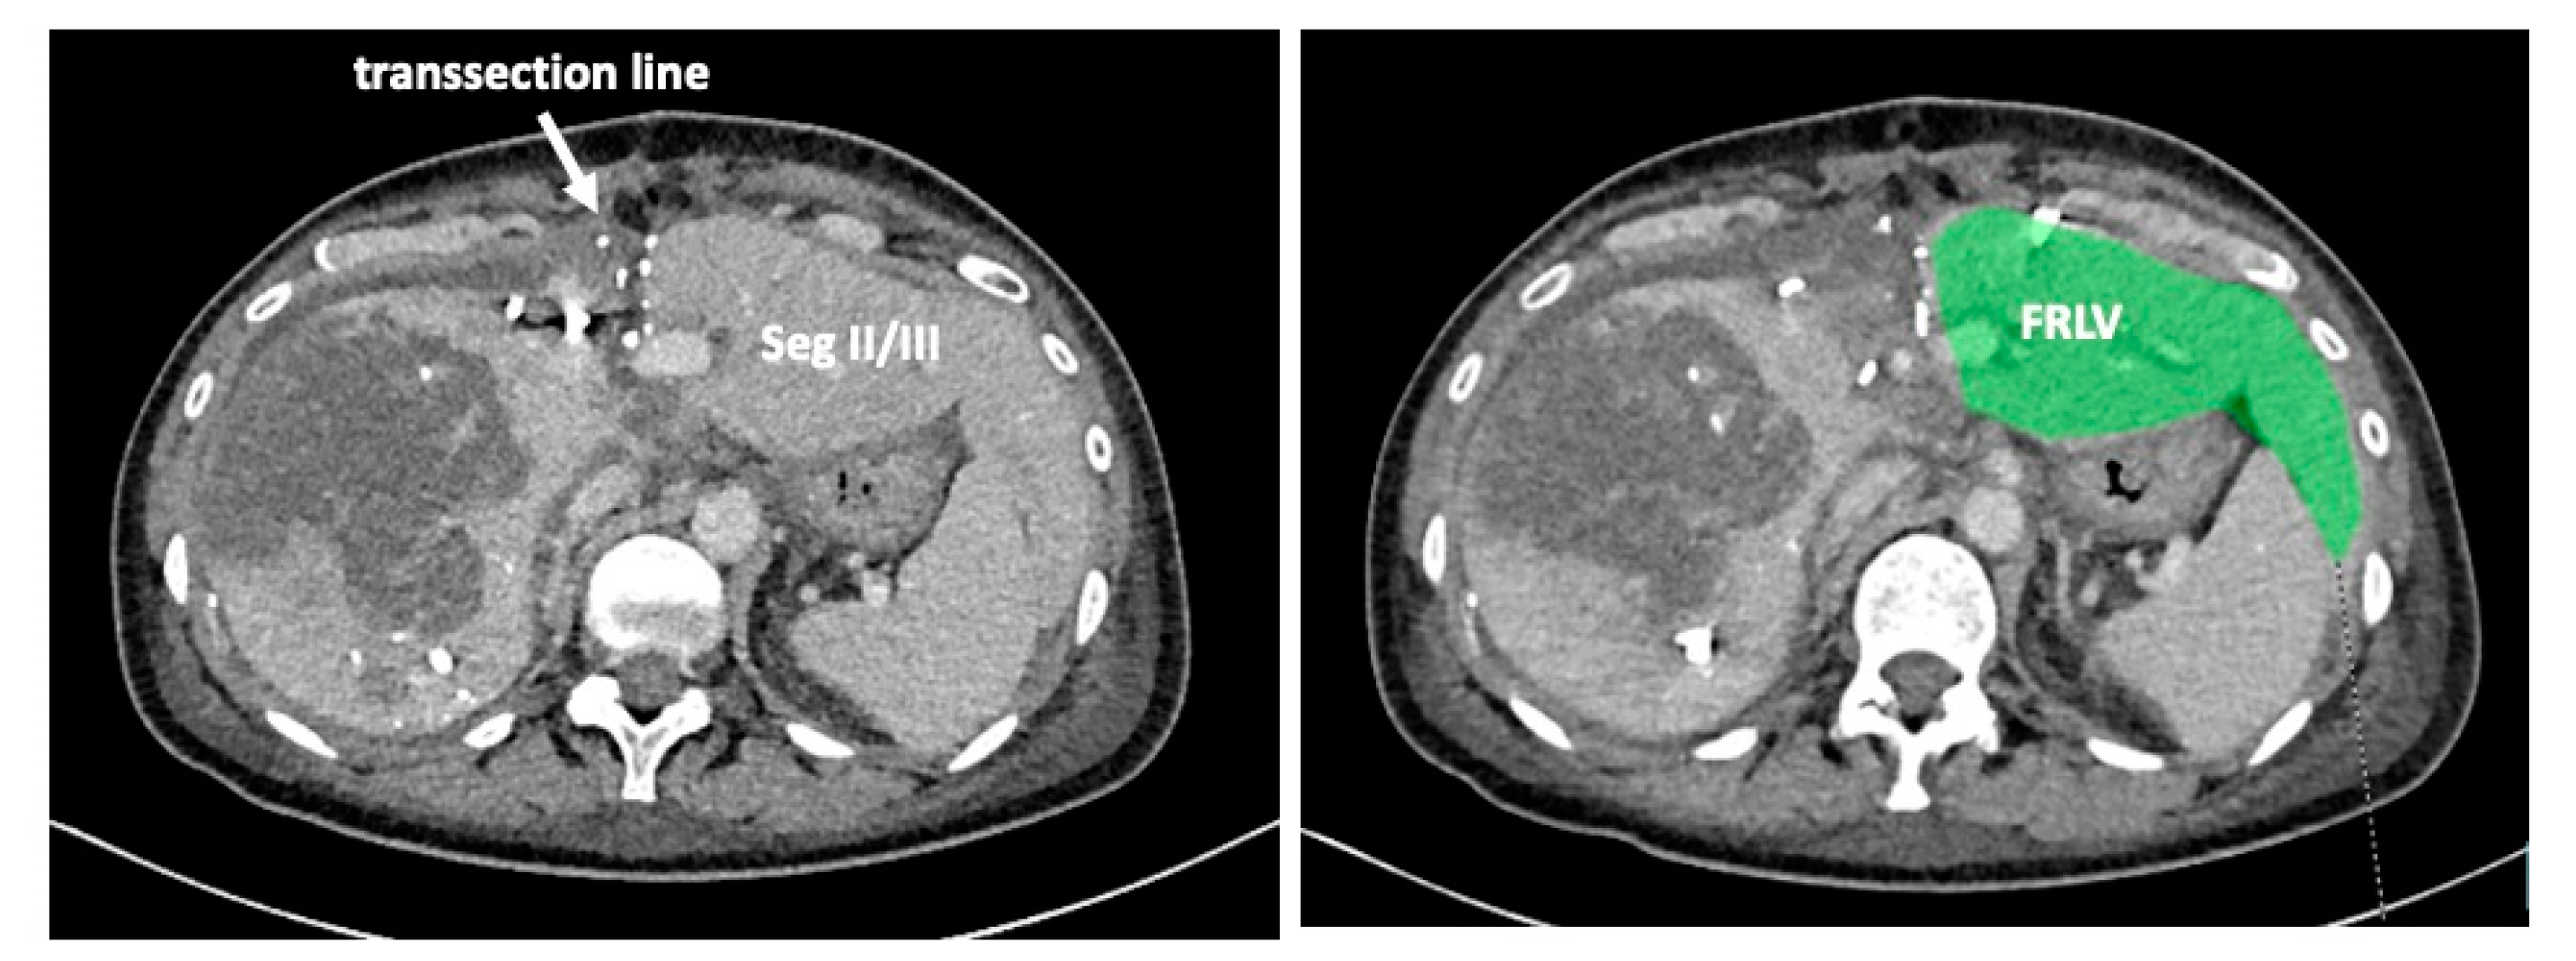

To complete in-situ splitting, the liver capsule is incised on the right side of the falciforme ligament and in the sulcus arantii. The parenchyma between segments II/III and I/IV is then divided (Figure 3). The structures to be transected in the future, i.e., all arterial and biliary branches to segments I and IV-VIII, as well as the right and middle hepatic veins, are marked by vessel loops that are fastened with titanium clips avoiding strictures of the vessels (Figure 4 and Figure 5). These remain in situ for easier identification during the second procedure. The future resection specimen is enveloped in a plastic foil (3M™ Steri ™ Drape Isolationsbeutel, 1003, 49 cm × 49 cm) to prevent adhesions in particular to the vena cava and at the resection margin.

On day 7 after the operation, CT-volumetry and, potentially, (99 m)Tc-mebrofenin-hepatobiliary-scintigraphy are performed. Alternative function tests may be used, according to the centers’ experience. We strongly recommend repeating the volumetric and functional analyses with the identical technique as used before the first step of the operation. This is repeated on a weekly basis until the necessary volume and function are reached (Figure 6). After sufficient growth of the remnant liver volume, i.e., a volume of >0.6% of the body weight or >25% of functional liver volume, and a cut-off value in the scintigraphy of 2.7%/min/m2 is achieved, completion hepatectomy is scheduled. In the case of prior chemo- or immunotherapy, the cut-off value of functional liver value may vary and additional investigations such as a (99 m)Tc-mebrofenin-hepatobiliary-scintigraphy are even more important. Some authors advocate more than 35% of functional liver volume in these conditions. During the second operation, a thorough exploration of the abdomen is performed, and the plastic foil is removed (Figure 7). Under the guidance of the vessel loops the previously marked arterial and biliary branches to the resection specimen, as well as the right and middle hepatic veins are divided, and the specimen is removed. If necessary, reconstructions of vessels and biliary structures are performed (Figure 8 and Figure 9).

Figure 3. A complete transsection between liver segments II/III and I/IV is recommended to render the second procedure as easy as possible. (A): During the first procedure. The vena cava is easily seen. (B): During the second procedure after division of the arteries and bile ducts to the right and caudate lobe. Removal of the resection specimen is safe and fast without further preparation or dissection.

Figure 6. The functional residual liver volume (FRLV) is measured on a weekly basis until a sufficient volume is reached.